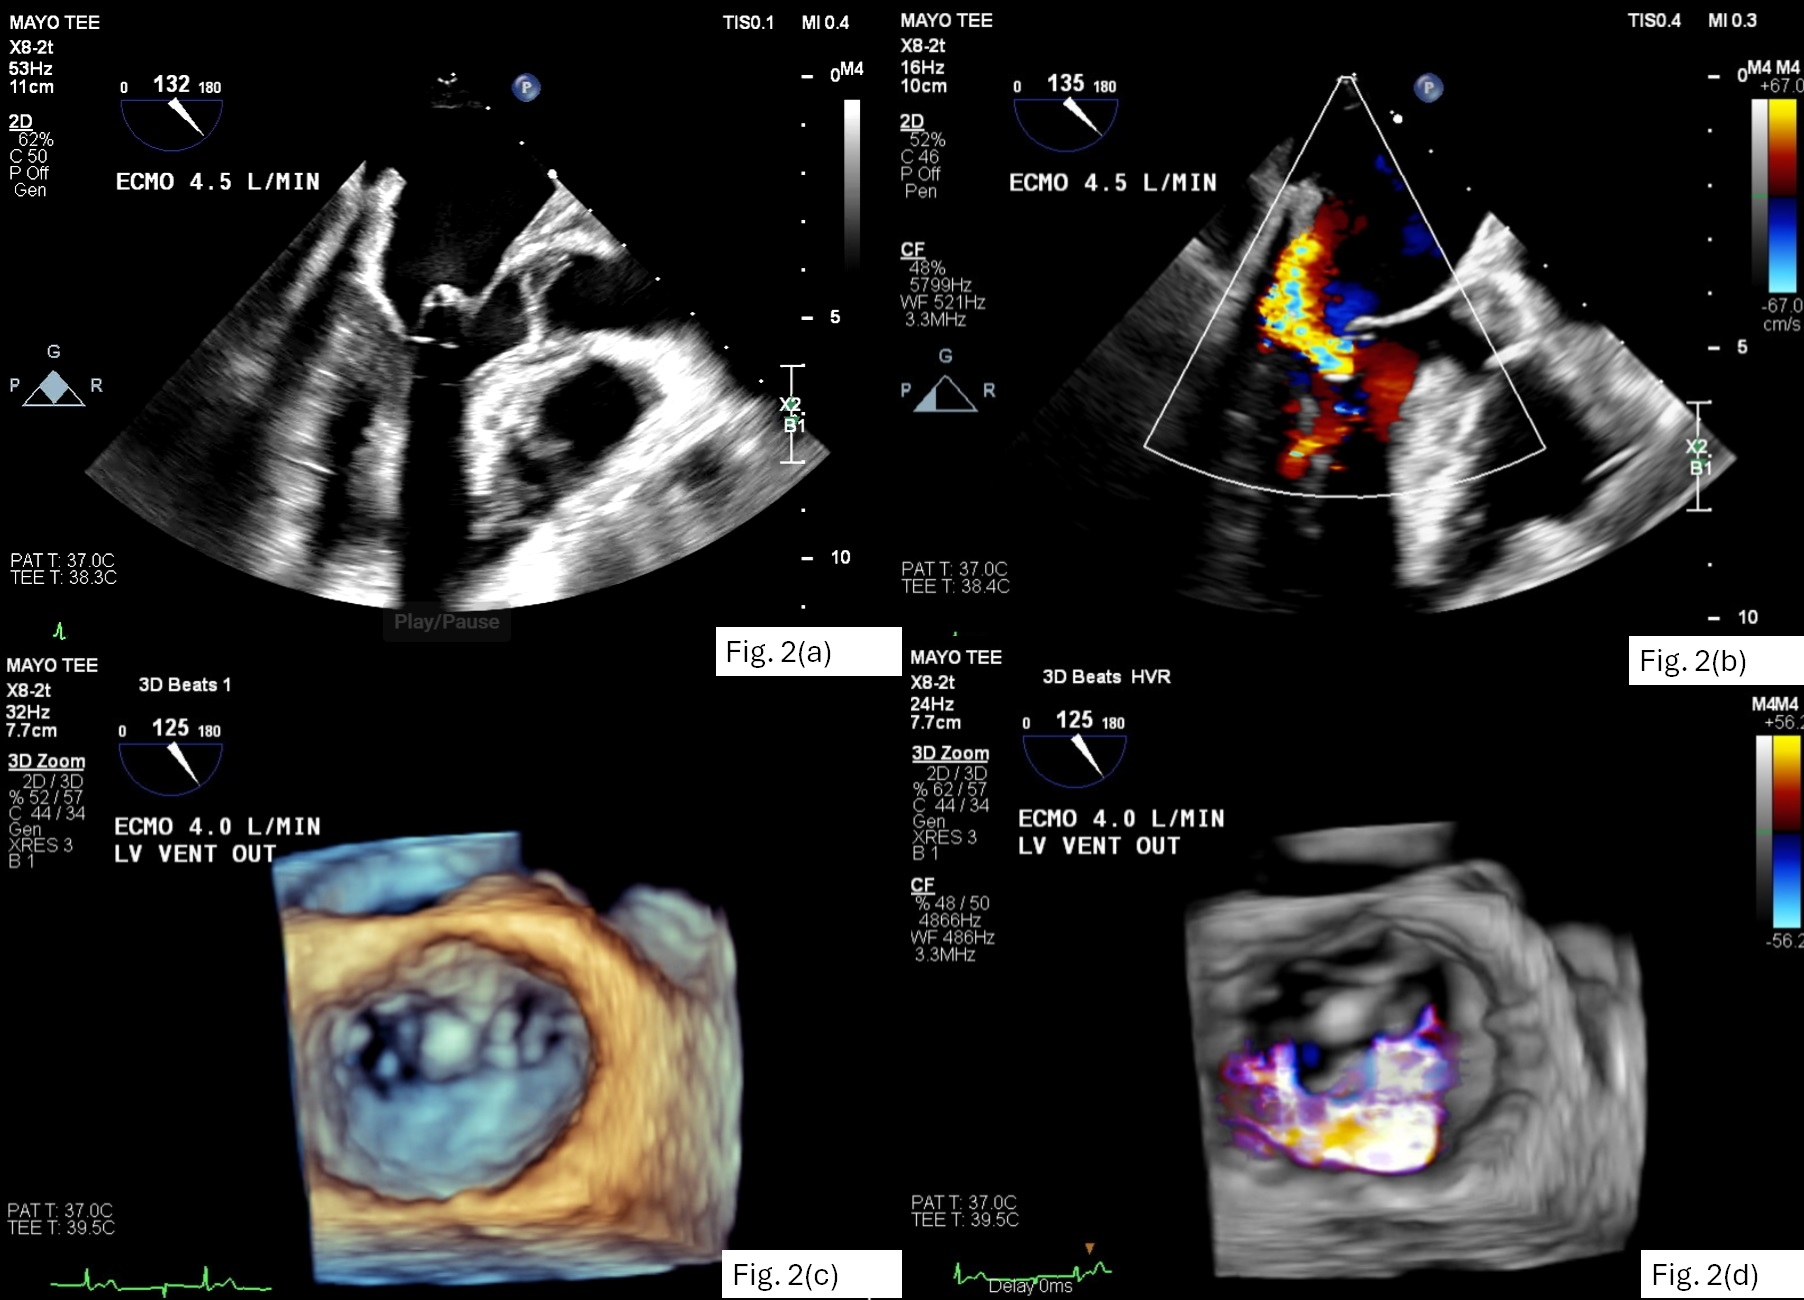

The patient was brought to the OR for mediastinal debridement and removal of the LV vent for the purpose of assessing ventricular function and improving arterial pulsatility. Pulse pressure remained negligible at an ECMO flow of 4.5 L/min. Transeosphageal echocardiography (TEE) demonstrated extensive thrombosis of the aortic root, particularly involving the right and non-coronary sinuses (Fig 1a). The aortic valve (AV) did not open. Patency of the left main coronary ostium was evident by color Doppler (Fig 1b) although no right coronary artery (RCA) flow could be visualized. The tip of LV vent was seen tenting the anterior leaflet of mitral valve (MV) causing significant regurgitation. (Fig. 2a-d)

After vent removal, LV contraction gradually increased and the AV began to open. This progressively dislodged thrombus from the aortic root. At the conclusion of imaging, there was a highly mobile, bi-lobed thrombus attached to the sinotubular junction (Fig 1c-d). Right ventricular (RV) function remained severely reduced. Moderate mitral regurgitation persisted, arising from A2 leaflet prolapse.